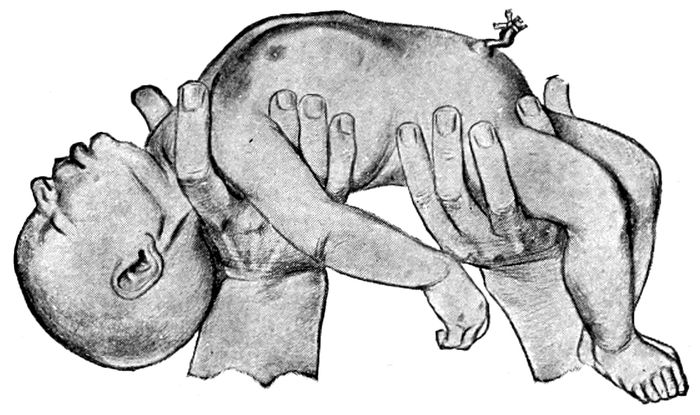

Extraction of the breech |

170 |

| |

| 64. |

Breech delivery. Extraction of the trunk |

171 |